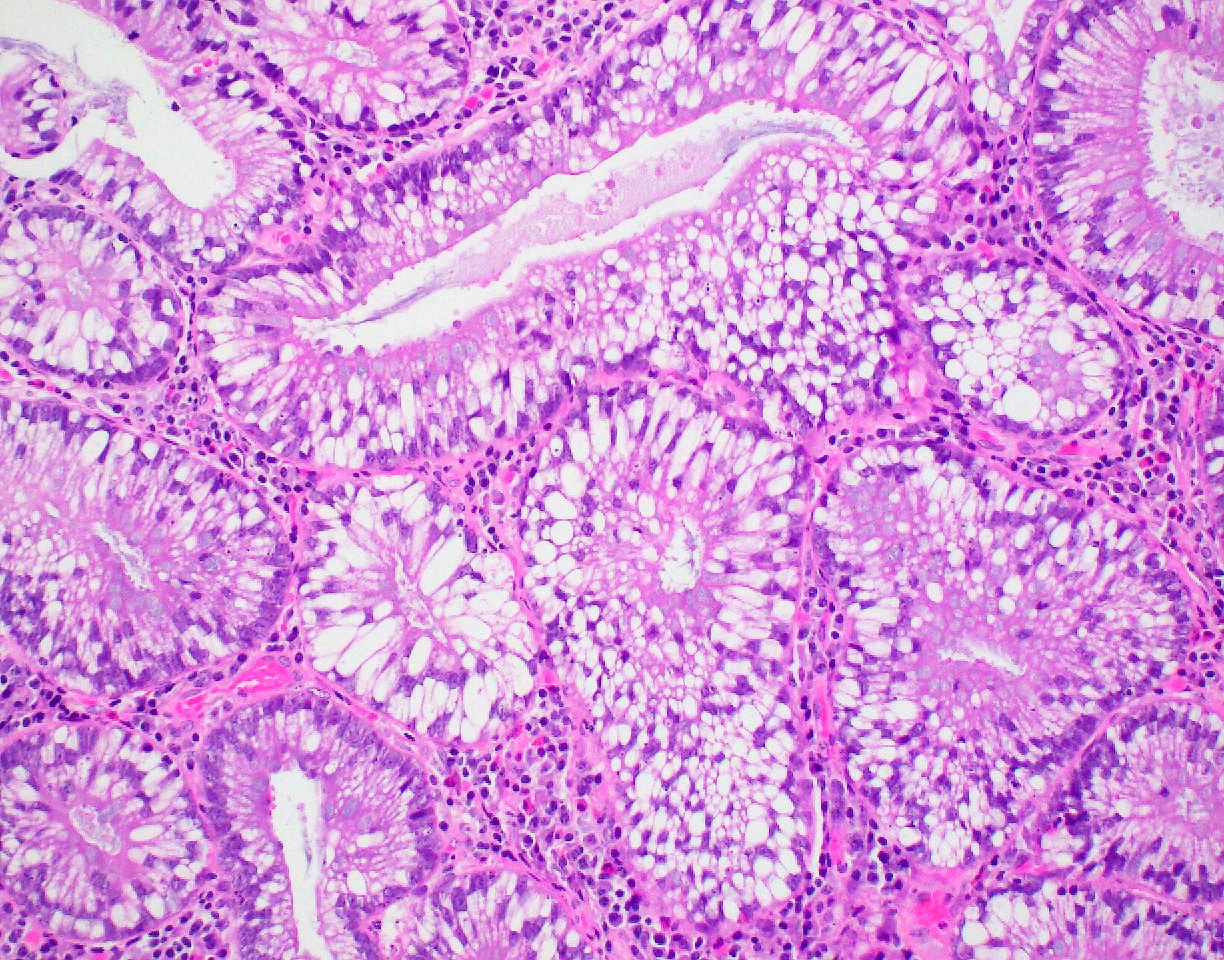

Microscopic (histologic) description

- Polypoid colonic mucosa covered with dysplastic epithelium comprised of hyperchromatic, elongated nuclei arranged in a pseudostratified manner

- Dysplasia is typically low grade but may also be high grade, with architectural (cribriforming, luminal necrosis) and cytologic changes (vesicular chromatin, nucleoli, loss of basal polarity)

- Abrupt transition from normal to dysplastic mucosa is commonly present

- Variable amounts of mucin loss

- Metaplasia may be present: osseous, squamous or Paneth cells (J Clin Pathol 2005;58:220, J Surg Oncol 1984;26:130)

- Pseudoinvasion can mimic progression to adenocarcinoma but displaced glands are benign and surrounded by lamina propria and often hemosiderin (Mod Pathol 2015;28:S88)

- May rarely show clear cell features (Am J Surg Pathol 2010;34:1344)

Microscopic (histologic) images

Contributed by Andrew L.J. Dunn, M.D. and Christopher Hartley, M.D.